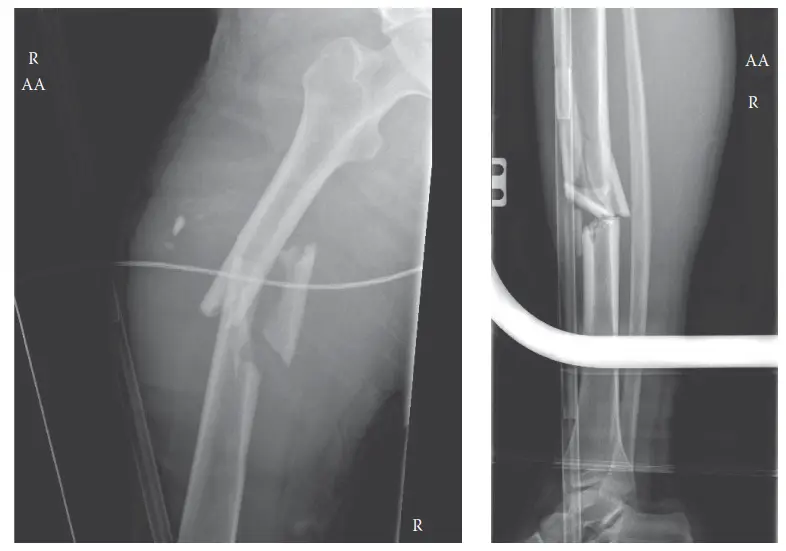

إصابة الركبة العائمة هي كسر شديد في عظم الفخذ والساق بنفس الطرف، وتحدث غالباً نتيجة حوادث عالية الطاقة. تتطلب جراحة دقيقة لإعادة الاستقرار والوظيفة، مع التركيز على إعادة التأهيل المتخصص لضمان أفضل النتائج وتجنب المضاعفات طويلة الأمد.

تُعد "إصابة الركبة العائمة" (Floating Knee Injury) من أخطر الإصابات العظمية وأكثرها تعقيداً التي قد تصيب الطرف السفلي. سُميت بهذا الاسم لأنها تتضمن كسراً متزامناً في عظم الفخذ (الفخذ) وعظم الساق (القصبة) في نفس الطرف، مما يجعل مفصل الركبة "عائماً" أو غير مستقر بين عظمتين مكسورتين. هذه الإصابة، التي وصفها لأول مرة الدكتور ماكنيور عام 1953 وصنفها الدكتور فريزر عام 1970، تنتج عادةً عن حوادث عالية الطاقة، مثل حوادث السيارات الخطيرة، السقوط من ارتفاعات عالية، أو حوادث دهس المشاة.

على الرغم من أن إصابات الركبة العائمة نادرة نسبياً، حيث تمثل حوالي 0.5-2% من جميع كسور العظام الطويلة، إلا أنها ترتبط بنسبة عالية من الإصابات المتعددة في أجزاء أخرى من الجسم (Polytrauma)، والتي قد تهدد الحياة. تشمل هذه الإصابات المرتبطة صدمات الرأس، وإصابات الصدر والبطن، بالإضافة إلى أضرار جسيمة للأوعية الدموية أو الأعصاب في الطرف المصاب. على سبيل المثال، يمكن أن يحدث إصابة للشريان المأبضي (Popliteal Artery) في 8-15% من الحالات، بينما تُسجل إصابات الأعصاب الشظوية أو الظنبوبية في 10-30% من الحالات. كما أن متلازمة الحيز (Compartment Syndrome)، وهي حالة تهدد الطرف، تحدث أيضاً بنسبة ملحوظة.